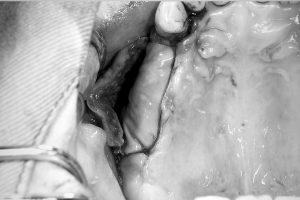

⑤メンブレンをピンで固定

人工骨の形が崩れないように、 コラーゲンメンブレン(膜)で覆い、

メンブレンがずれないようにチタンピンで 固定する。

※メンブレンの使用目的

骨と歯肉では回復速度が異なり、 骨は1ヶ月に1ミリ 歯肉は1週間で1ミリ回復する。

メンブレンを置かない場合、歯肉に骨の 回復が負けてしまい、

軟組織が人工骨に 入り込んで、骨がしっかり出来なくなる。